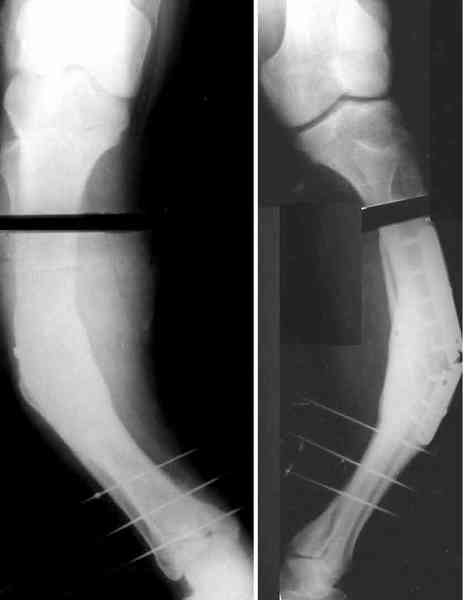

Для продолжения темы - несколько картинок.

Пациент 30 лет, лет пять назад оперирован по поводу перелома голени пластиной. Находясь на героине, нарушил режим, пошел, сломал и ногу и

пластину, но перелом сросся.

В приложении - внешний вид и рентген.

Мнения?

Лукавить не буду, я его уже вылечил. Но применил немного необычную тактику по отношению к пластине - результат после обсуждения...

a>> В приложении - внешний вид и рентген.

a>> Мнения?

Александр, как раз уровень остеотомии подробнее - на вершине деформации? Там Сломанная пластина.

Там не винты (может, плохо видно), а сломанная пластина, вросшая в кость.

a> Там не винты (может, плохо видно), а сломанная пластина, вросшая в

a> кость.

Пластинку и винты мне удалось разглядеть только на профильной проекции, точнее, трехчетвертной, судя по виду коленного сустава (правый снимок). На фасной - вообще не могу разобрать, где она :( Но, в конце концов, можно и не видя ее сказать, что уровень остеотомии может быть и другим, ниже или выше пластинки, придется только компенсировать смещение по ширине, которое появится при полном устранении угла не на вершине.